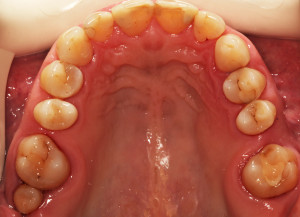

Do kliniki Stomatologia Bez Bólu zgłosiła się pacjentka, lat 61 z problemem nadwrażliwości zębów. Po przeprowadzonym wywiadzie stwierdzono spożywanie sporej ilości sezonowych owoców (truskawki, wiśnie, czereśnie, czarna porzeczka), nawet 3 razy dziennie. Następnie wykonano badanie wewnątrzustne. Stwierdzono obecność płytki nazębnej, ciemnego osadu oraz kamienia nazębnego na części trzonowców:

Wykonano higienizację jamy ustnej poprzez usunięcie kamienia nazębnego skalerem ultradżwiękowym, zdjęciem osadu i płytki nazębnej poprzez piaskowanie air flow plus oraz classic, a następnie wypolerowaniu gumką ze specjalistyczną pastą polerską: